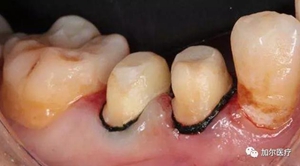

2、越貴的烤瓷牙材料,壽命越久是真是假?

不能有一勞永逸的想法,材料再這么好,烤瓷牙都是有自己的壽命限制,最多也就10年左右,而且再貴的材料都離不開醫(yī)生技術和后期維護,兩者缺一不可,要注意的是牙齦邊緣變色得及時換掉烤瓷牙,有條件最好選擇內(nèi)冠全瓷,有利增加烤瓷牙的

使用壽命。

想辨別烤瓷牙冠是否有問題,先感覺烤瓷牙邊緣有沒有存在臭味,沒有說明邊緣密合,有的話觀察牙齦顏色,記得選擇烤瓷牙材料不是越貴越好,適合自己的才最重要